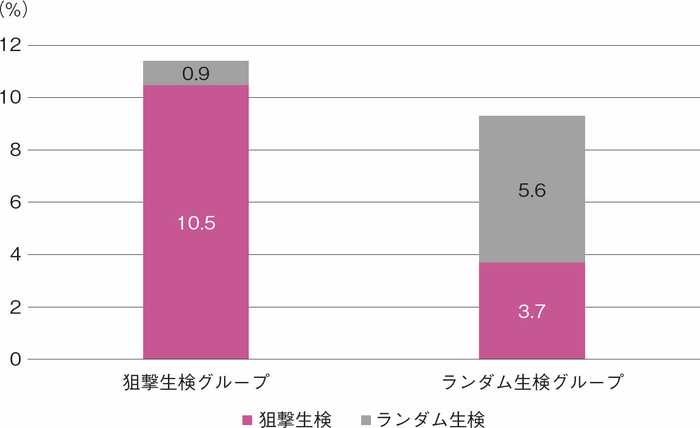

UC関連大腸腫瘍の肉眼的特徴として,偶発的に発生する散発性腫瘍病変に比して平坦型の割合が多く,病変の境界が不明瞭であることが多いことが報告されている2,11)。したがって内視鏡検査による通常観察では腫瘍病変を検出することが容易ではないと考えられており,ランダム生検すなわち10 cmおきに4個ずつ(最低33個以上)生検を行うことが推奨されてきた。一方で本邦においてランダム生検と狙撃生検を比較する腫瘍病変検出率を検討した多施設共同ランダム化比較試験が行われ,ランダム生検群で腫瘍病変が検出された患者の割合は9.3%,狙撃生検群では11.4%であり,両群の検出率が同等であり,かつ生検数は狙撃生検群で有意に少ないことが示された12)。したがって炎症が安定している症例では狙撃生検が推奨される。一方でランダム生検により腫瘍検出率が15%上昇すること13)やランダム生検でなければ検出困難と思われる病変が存在することも報告されている14)。以上より患者の病歴や内視鏡所見,内視鏡医の技量などを参考に,ランダム生検の施行を検討することも本ガイドラインのステートメントに記載されている(CQ 8)。

図3 RCTによる狙撃生検とランダム生検によるdysplasia検出能(各グループの検出率)